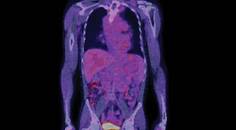

Liquid biopsy involves identifying and analyzing circulating biomarkers in blood, cerebrospinal fluid (CSF), and other bodily fluids to gather molecular and genomic information for tumor characterization (Figure). Whereas blood-based biomarkers are commonly used to monitor treatment response and disease progression in many solid organ cancers, there are no established circulating biomarkers for assessing response in gliomas.2,3 We provide an overview of the current state of circulating biomarkers in gliomas and their role in the evolving landscape of glioma management.